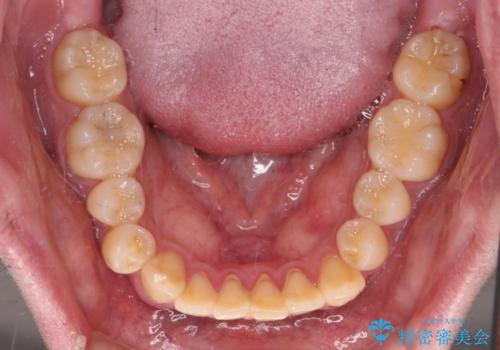

- 前歯のデコボコとクロスバイトを気にして来院された患者様です。

インビザラインでもワイヤー装置でも矯正治療は可能でしたが、煩わしい自己管理なしに短期間で治療を行いたいとのことで、目立たないワイヤー装置にて治療を行うこととしました。